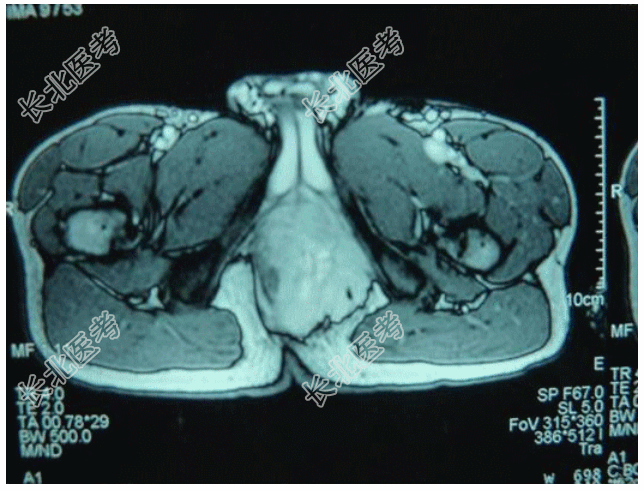

- [材料题] 患者男,18岁,会阴肿块,影像学表现如图所示。行穿刺活检,镜下形态如图所示。

- 简答题1、首先考虑的诊断是?

- 简答题2、该肿瘤的染色体异常表现为?

- 简答题3、该肿瘤好发于?